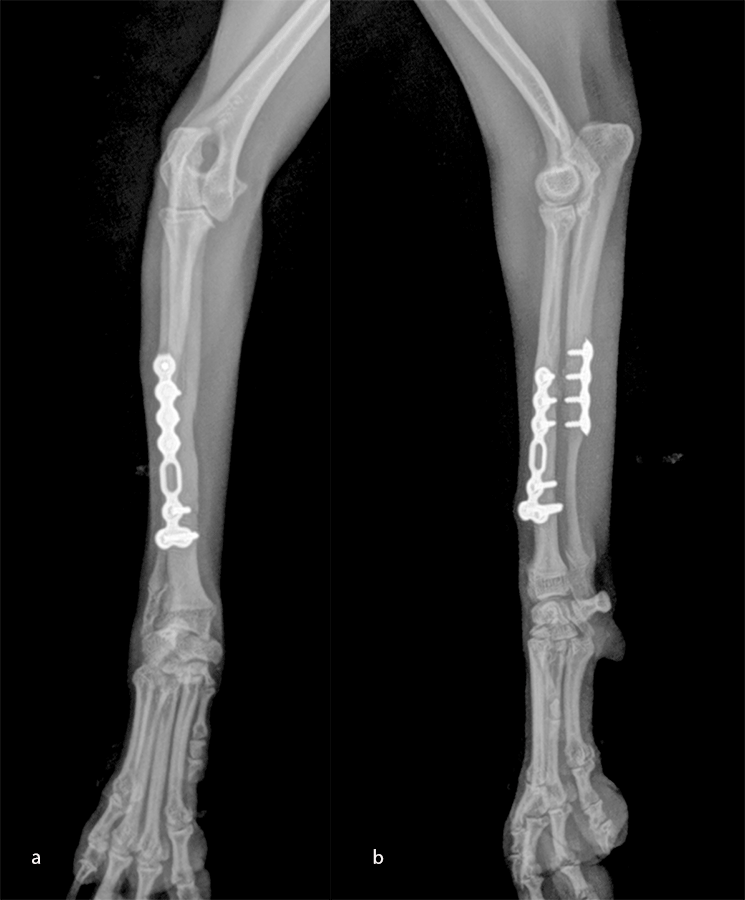

An open but do-not-touch approach was performed, and the plate was fixed with both cortex screws and locking screws for both plates (Fig 12). After 4 months, the fractures were totally healed with normal bone growth and the dog had a complete functional recovery (Fig 13).